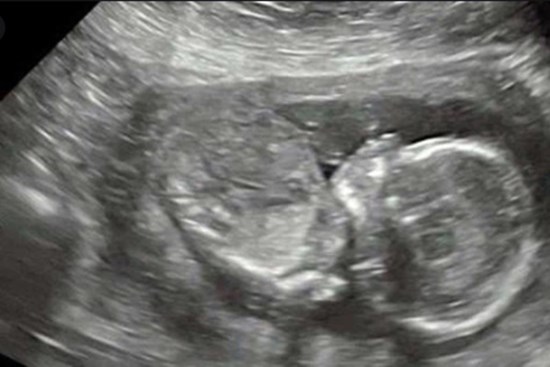

Kỳ tích tại BV Phụ sản Hà Nội: Hai trẻ song sinh chào đời cách nhau 13 tuần

Sau khi bé gái đầu tiên sinh non ở tuần 26, các bác sĩ Bệnh viện Phụ sản Hà Nội nỗ lực giữ thai còn lại trong tử cung thêm 13 tuần, giúp bé trai chào đời khỏe mạnh.

Bệnh viện Phụ sản Hà Nội: Công bố ca song thai cùng trứng cực kỳ đặc biệt, thế giới mới ghi nhận 1 trường hợp

Ngày 9/11, Bệnh viện Phụ sản Hà Nội công bố ca bệnh song thai cùng trứng nhưng khác nhau về kiểu hình và kiểu gene.